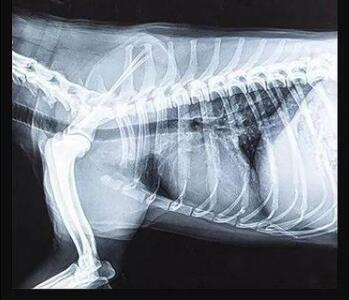

傳統(tǒng)的平板探測器,相當(dāng)于普通攝像機(jī),對(duì)于拍攝急促呼吸狀態(tài)下的寵物,成像效果存在著明顯缺陷。而新一代寵物平板探測器,宛如高速攝像機(jī),能夠清晰記錄動(dòng)物每一個(gè)精準(zhǔn)瞬間。

寵物dr專用平板拍攝效果